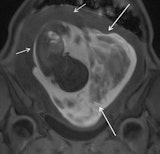

- Adnexal mass: Ultrasound can assess most masses; however, MRI can provide further characterization, particularly for evaluating their hemorrhagic content.

- Ovarian torsion: MRI should be performed after inconclusive ultrasound and can detect hemorrhagic infarction.